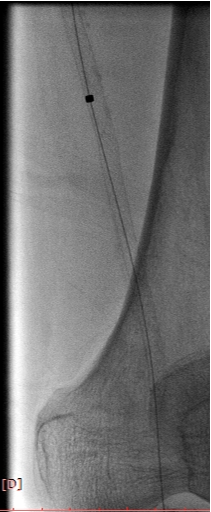

病例-2 男性,69岁,外院股腘动脉支架后再狭窄DCB后1年复发,右侧为重